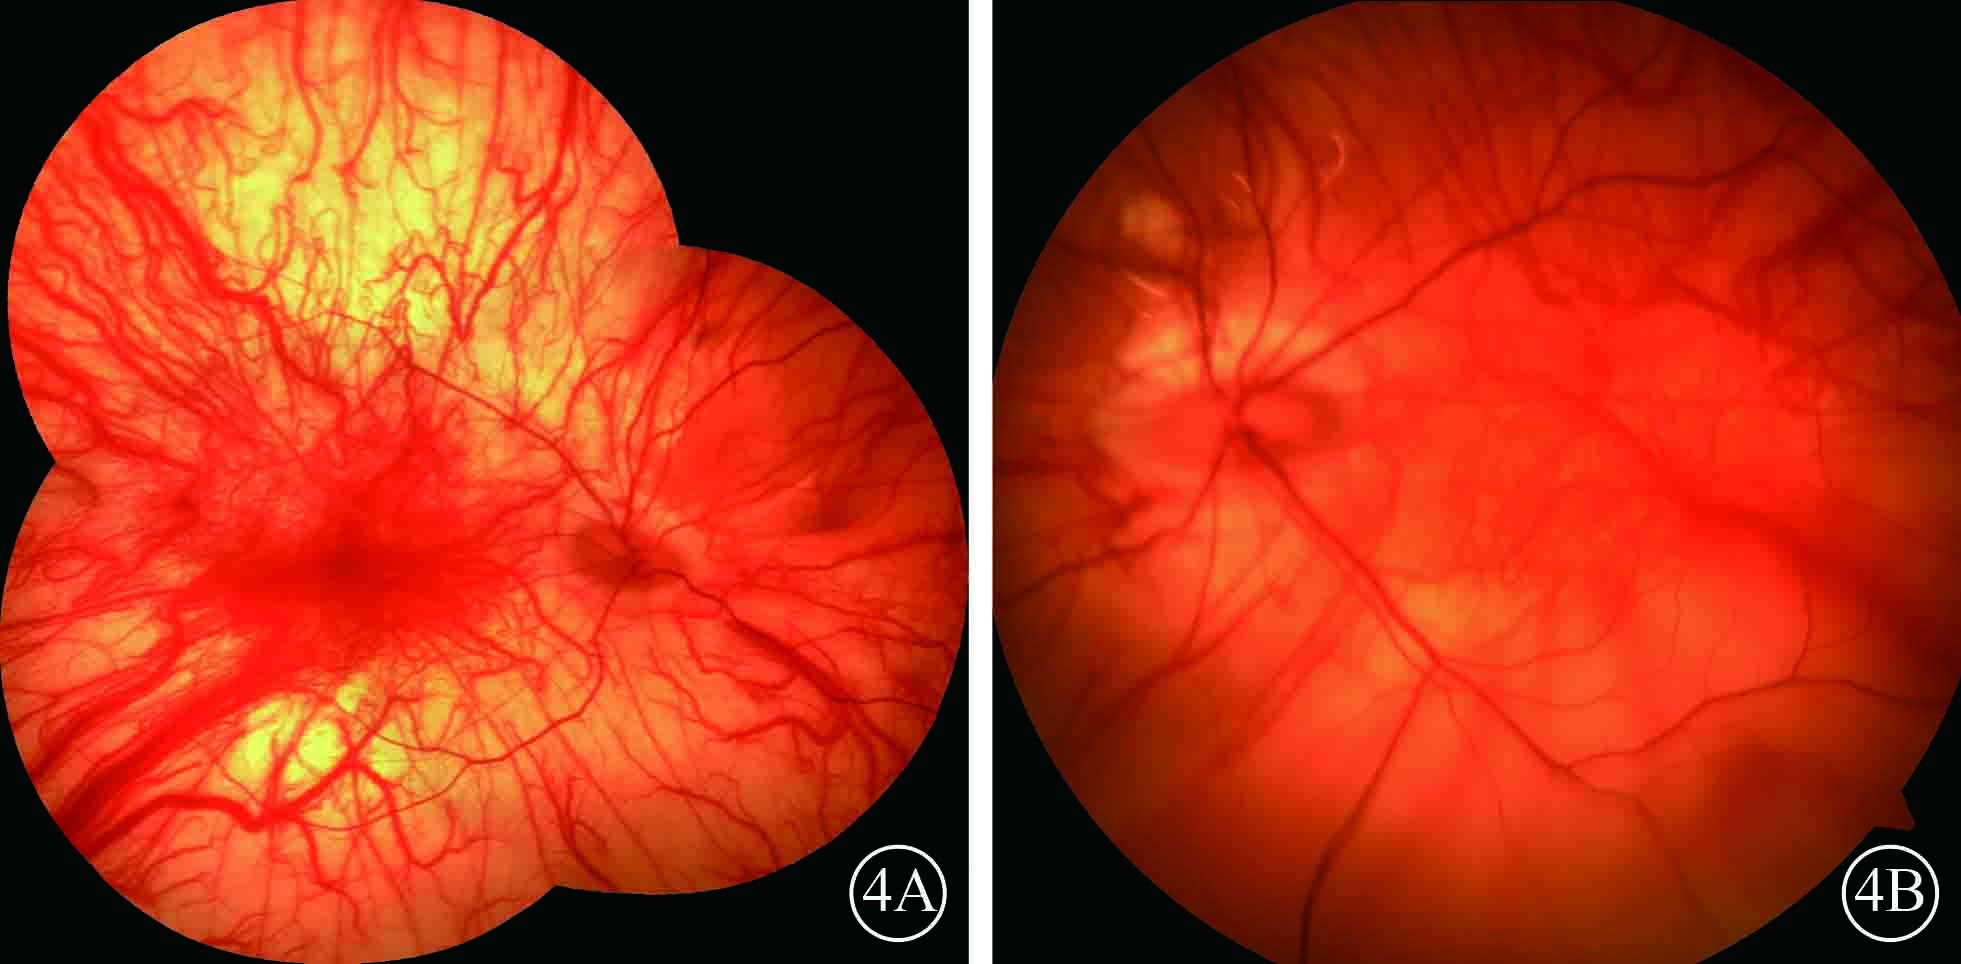

圖4

末次隨訪雙眼彩色眼底像。4A. 右眼,視網膜復位良好;4B. 左眼,下方視網膜脫離

圖4

末次隨訪雙眼彩色眼底像。4A. 右眼,視網膜復位良好;4B. 左眼,下方視網膜脫離

患者男,35歲。因體檢發現雙眼視網膜脫離1月余于2015年3月12日來我院眼科就診。患者自幼皮膚、毛發、虹膜無色素;雙眼視力差、畏光。否認外傷史、家族史。眼部檢查:右眼視力數指/30 cm,左眼視力0.1;雙眼矯正視力均無提高。雙眼眼瞼皮膚及睫毛均無色素;眼球水平震顫;角膜透明,瞳孔圓,虹膜半透明;晶狀體透明。雙眼眼底呈橙色。右眼全視網膜脫離,左眼0~8點時鐘位視網膜脫離(圖1);雙眼視網膜裂孔均窺不清。A型超聲檢查,右眼、左眼眼軸長度分別為26、28 mm。診斷:(1)雙眼孔源性視網膜脫離(疑似);(2)雙眼高度近視;(3)眼皮膚白化病。分別于2015年3月23日、5月11日行左眼、右眼視網膜復位手術。采用標準25G經睫狀體平坦部玻璃體切割手術。手術中見左眼視網膜裂孔分別位于 1、2、4、6點時鐘位,右眼裂孔位于8、11點時鐘位。先采用眼內電凝對裂孔邊緣進行標記,電凝處理后裂孔邊緣呈白色外觀(圖2);視網膜復位后,采用視網膜冷凍替代常規激光光凝對裂孔進行封閉;最后進行硅油眼內填充。雙眼均于手術后3個月行硅油取出手術。硅油取出后3個月,雙眼視網膜復位良好,眼底呈橙色,透見脈絡膜大血管(圖3);6個月,右眼視網膜復位良好,左眼下方視網膜再次脫離。于2016年2月1日再次行左眼視網膜復位手術、硅油填充。2016年12月27日隨訪,右眼視網膜復位良好;左眼硅油填充,下方視網膜仍有局部脫離(圖4)。

患者男,35歲。因體檢發現雙眼視網膜脫離1月余于2015年3月12日來我院眼科就診。患者自幼皮膚、毛發、虹膜無色素;雙眼視力差、畏光。否認外傷史、家族史。眼部檢查:右眼視力數指/30 cm,左眼視力0.1;雙眼矯正視力均無提高。雙眼眼瞼皮膚及睫毛均無色素;眼球水平震顫;角膜透明,瞳孔圓,虹膜半透明;晶狀體透明。雙眼眼底呈橙色。右眼全視網膜脫離,左眼0~8點時鐘位視網膜脫離(圖1);雙眼視網膜裂孔均窺不清。A型超聲檢查,右眼、左眼眼軸長度分別為26、28 mm。診斷:(1)雙眼孔源性視網膜脫離(疑似);(2)雙眼高度近視;(3)眼皮膚白化病。分別于2015年3月23日、5月11日行左眼、右眼視網膜復位手術。采用標準25G經睫狀體平坦部玻璃體切割手術。手術中見左眼視網膜裂孔分別位于 1、2、4、6點時鐘位,右眼裂孔位于8、11點時鐘位。先采用眼內電凝對裂孔邊緣進行標記,電凝處理后裂孔邊緣呈白色外觀(圖2);視網膜復位后,采用視網膜冷凍替代常規激光光凝對裂孔進行封閉;最后進行硅油眼內填充。雙眼均于手術后3個月行硅油取出手術。硅油取出后3個月,雙眼視網膜復位良好,眼底呈橙色,透見脈絡膜大血管(圖3);6個月,右眼視網膜復位良好,左眼下方視網膜再次脫離。于2016年2月1日再次行左眼視網膜復位手術、硅油填充。2016年12月27日隨訪,右眼視網膜復位良好;左眼硅油填充,下方視網膜仍有局部脫離(圖4)。

圖4

末次隨訪雙眼彩色眼底像。4A. 右眼,視網膜復位良好;4B. 左眼,下方視網膜脫離

圖4

末次隨訪雙眼彩色眼底像。4A. 右眼,視網膜復位良好;4B. 左眼,下方視網膜脫離